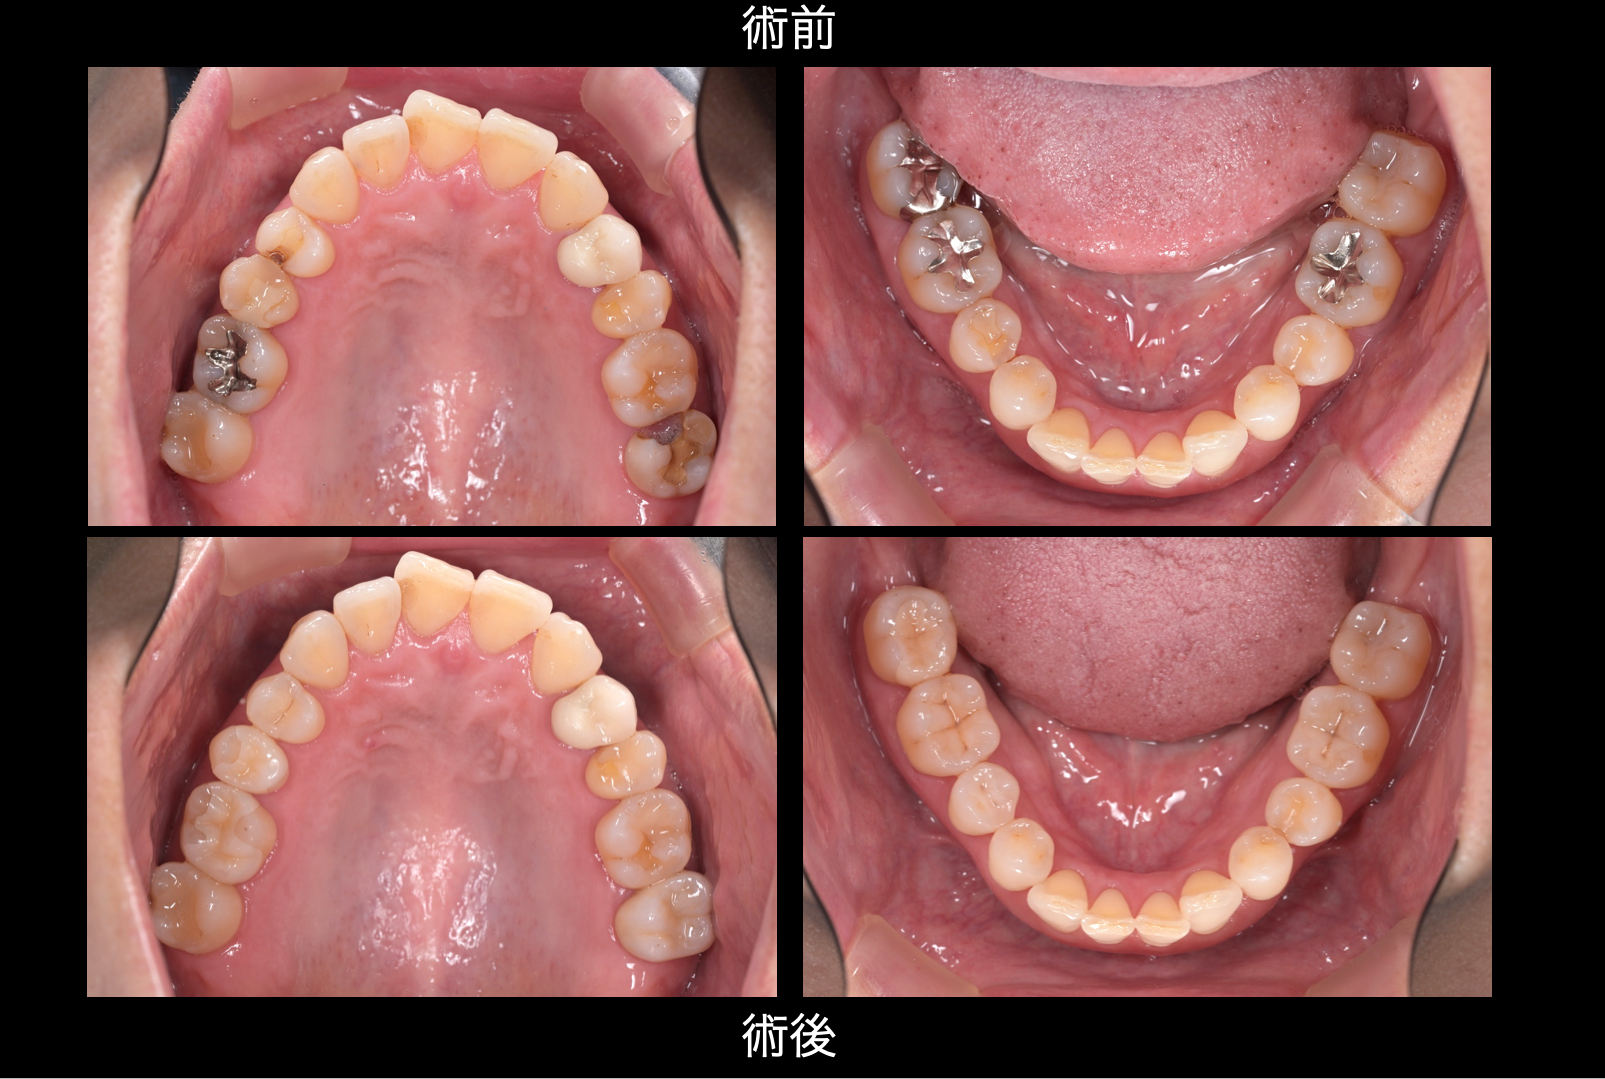

| 主訴 | 左下の虫歯が痛む |

|---|---|

| 治療内容 | 患者さんのご希望をカウンセリングでしっかり伺う。 貸切、オーダーメイド診療 |

| 治療期間 | 半年 |

| 治療費 | 1,320,000円(税込) |

| リスク・副作用 | 仮歯の脱離 |

保険治療を受けていたが、あまり良い対応では無かったとのこと。

虫歯は全てマイクロスコープ下で治療。

精度、色合わせにも徹底的にこだわっています。

歯を製作したいる歯科技工士は国内トップレベルの方々を厳選しています。